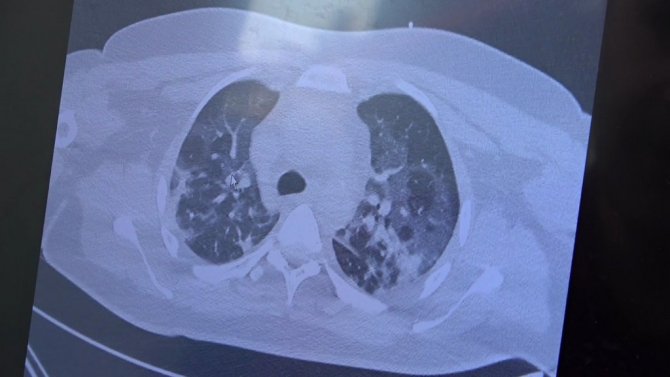

Gençlerin akciğer tomografilerini inceleyen Özkaya, "İki vaka örneği hakkında bilgi vermek istiyorum. İnsanlara bu işin bitmediğini anlatmamız lazım. 30 yaşında aşı olmamış bir hastamızın filminde çok yaygın akciğer hasarı var. Şu an kendisi yoğun bakımda tedavi alıyor. Öte yandan 25 yaşında bir hastamız var. İki doz kovid aşısını da olmamış. Ciddi akciğer tutulumları var. Çok ciddi solunum sıkıntısı ile kovid servisinde yatıyor. Şu an hasta profilimizin büyük bir kısmını bu durum oluşturuyor" ifadelerini kullandı.